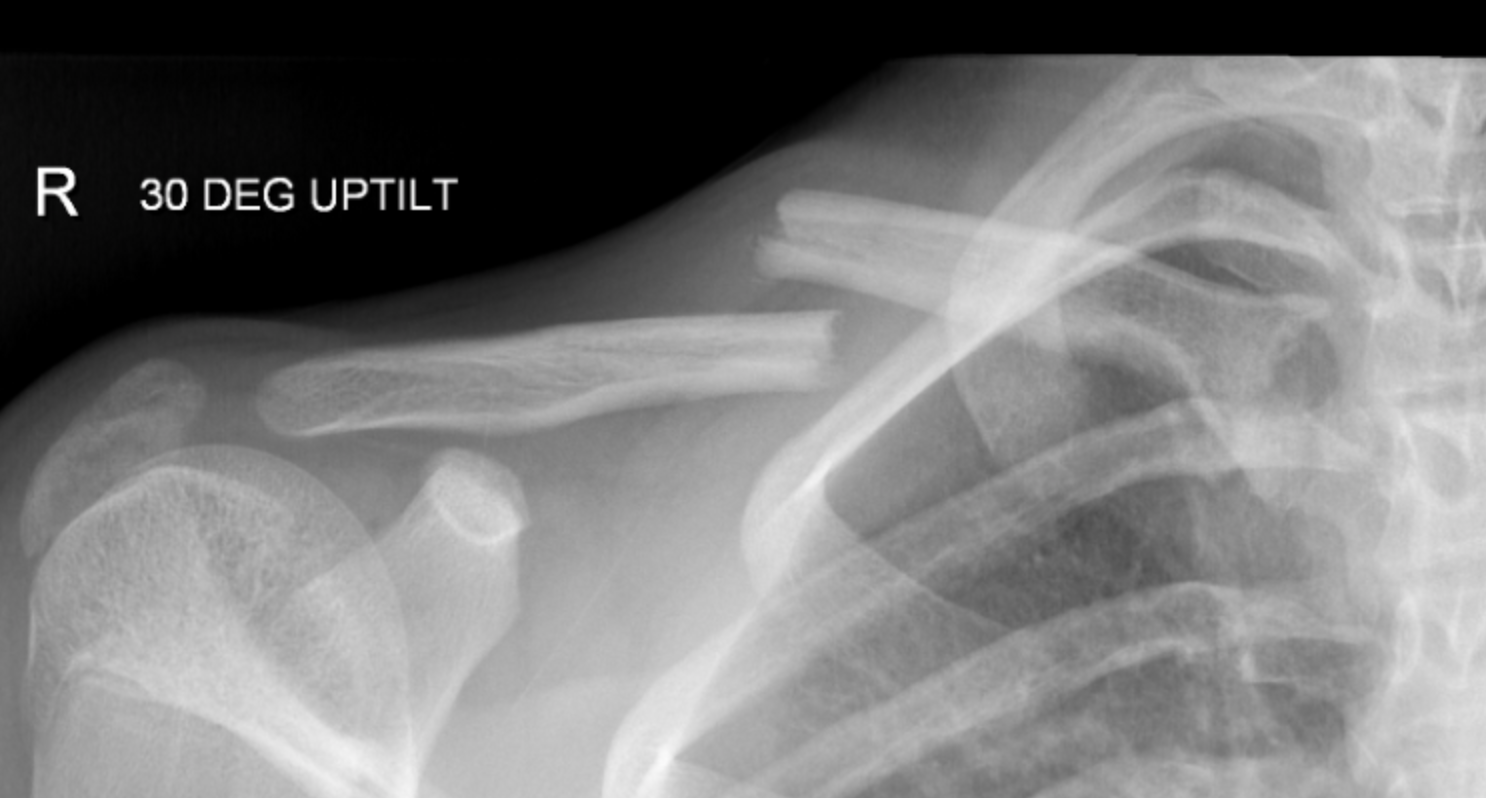

Collarbone is often fractured secondary to fall or direct blow to the shoulder. In adults, it takes about 6 to 8 weeks to heal completely. In children, the broken clavicle heals in 3 to 6 weeks. Reference: https://www.nhs.uk/conditions/broken-collarbone/ Image via: https://www.rch.org.au/clinicalguide/guideline_index/fractures/Clavicle_fractures_Emergency_Department/?slave_host=chimb.ca